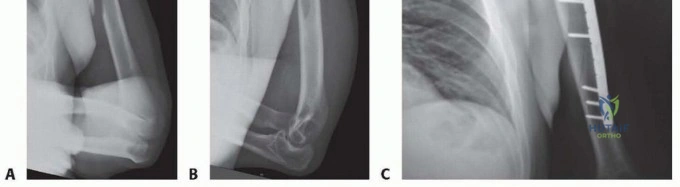

Imaging and Templating

Standard orthogonal radiographs, including an anteroposterior and true lateral of the entire humerus, are mandatory. The imaging must visualize the shoulder and elbow joints to rule out intra-articular extension. Computed tomography is rarely indicated for diaphyseal fractures unless there is suspicion of occult intra-articular extension at the distal humerus.

Digital templating is performed to determine the appropriate plate length. A general biomechanical rule for diaphyseal plating is to achieve a minimum of three to four bicortical screws (six to eight cortices) in both the proximal and distal main fracture fragments. A 4.5 millimeter narrow limited contact dynamic compression plate or locking compression plate is typically selected.

For simple fracture patterns (transverse or short oblique), absolute stability is the goal. If the obliquity allows, an interfragmentary lag screw is placed perpendicular to the fracture plane to generate interfragmentary compression. A 4.5 millimeter narrow plate is then contoured to the anterolateral aspect of the humerus. The plate is applied in a neutralization mode. If a lag screw cannot be placed, the plate is applied in a dynamic compression mode utilizing eccentrically drilled screws.

For comminuted or segmental fractures, relative stability is preferred. The fracture zone is bypassed without disturbing the comminuted fragments, preserving the local biology. A longer plate is utilized to span the fracture, acting as a bridge construct. Locking screws are highly beneficial in this scenario, particularly in osteoporotic bone, as they provide angular stability and reduce the risk of hardware pullout.

Clinical & Radiographic Imaging